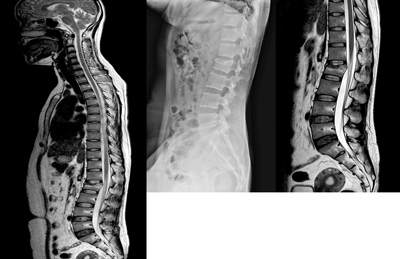

Medical imaging

Radiological examination is crucial in the diagnosis of SCI.

Plain x-rays may provide initial information on spinal injury, however, are not used to clear the trauma patient of injury. The patient should be cared for as a possible cervical vertebral injury.

A CT scan/MRI should be undertaken if the NEXUS criteria for cervical spine clearance have not been met, or the patient is unconscious. Should the patient exhibit any of the criteria as mentioned previously, then clinical examination is unreliable and radiographic assessment is advised. Where facilities do not have CT imaging available, then consultation with ARV and the MTS regarding retrieval and transfer should take place. X-ray imaging of the cervical spine is not suitable to clear the neck of the trauma patient. It may be appropriate to delay exhaustive imaging investigations if they are not going to alter management. Definitive imaging may be performed at the receiving specialist unit.

All SCI patients must have a chest x-ray. If head trauma or loss of consciousness has occurred, a CT brain is indicated. Consider further diagnostic imaging if available and indicated.